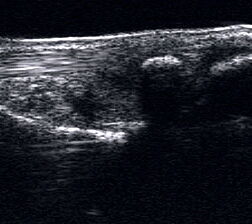

Peronealsehnenläsion

Lagerung: Rückenlage, Innendrehung des Beines

Schnittführung: TS und LS hinter dem Außenknöchel beginnen und die beiden Peronäalsehnen bis zur Basis des Metatarsale V durchmustern, für Longus-Sehne auch plantare Untersuchung in TS und LS (Abb. 39).

Referenzstrukturen: Fibulahinterkante, Basis Metatarsale V.

Befunde: Halophänomen und echoarme Verdickung bei akuter Tendinopathie, zunehmend inhomogen und echogen bis hin zu Teilrupturen bei chronischem Verlauf. Für die Erkennung von Teilrupturen sind TS in verschiedener Höhe besonders wichtig. Bei komplettem Riss zeigt sich der Sehnenstumpf wie eine Spargelspitze (Abb. 40). Der retrahierte Sehnenstumpf ist von Flüssigkeit und Hämatom umgeben.

Ein Teilriss der Peronaeus brevis Sehne mit Invagination der Peronaeus longus Sehne kann beim Peronaeal Tendon Split Syndrom beobachtet werden (Abb. 41 und 42).